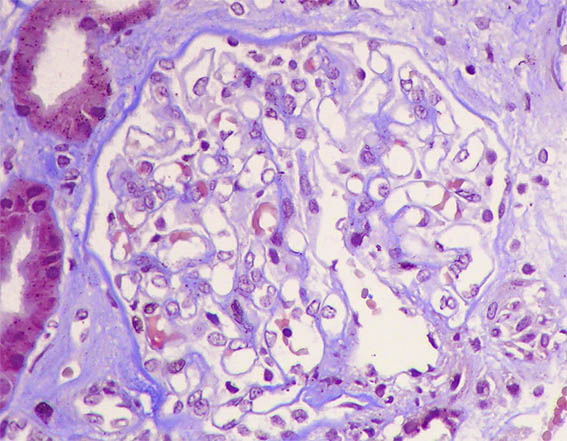

Figure 5. Methenamine-silver, X400.